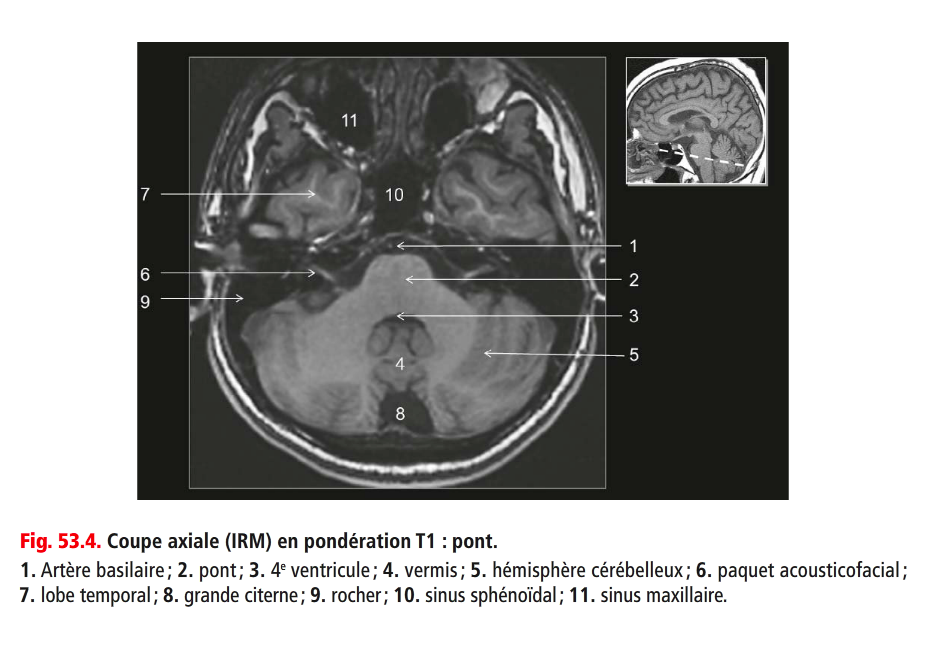

Coupe ?

Légende ?

Coupe ? Légende ?